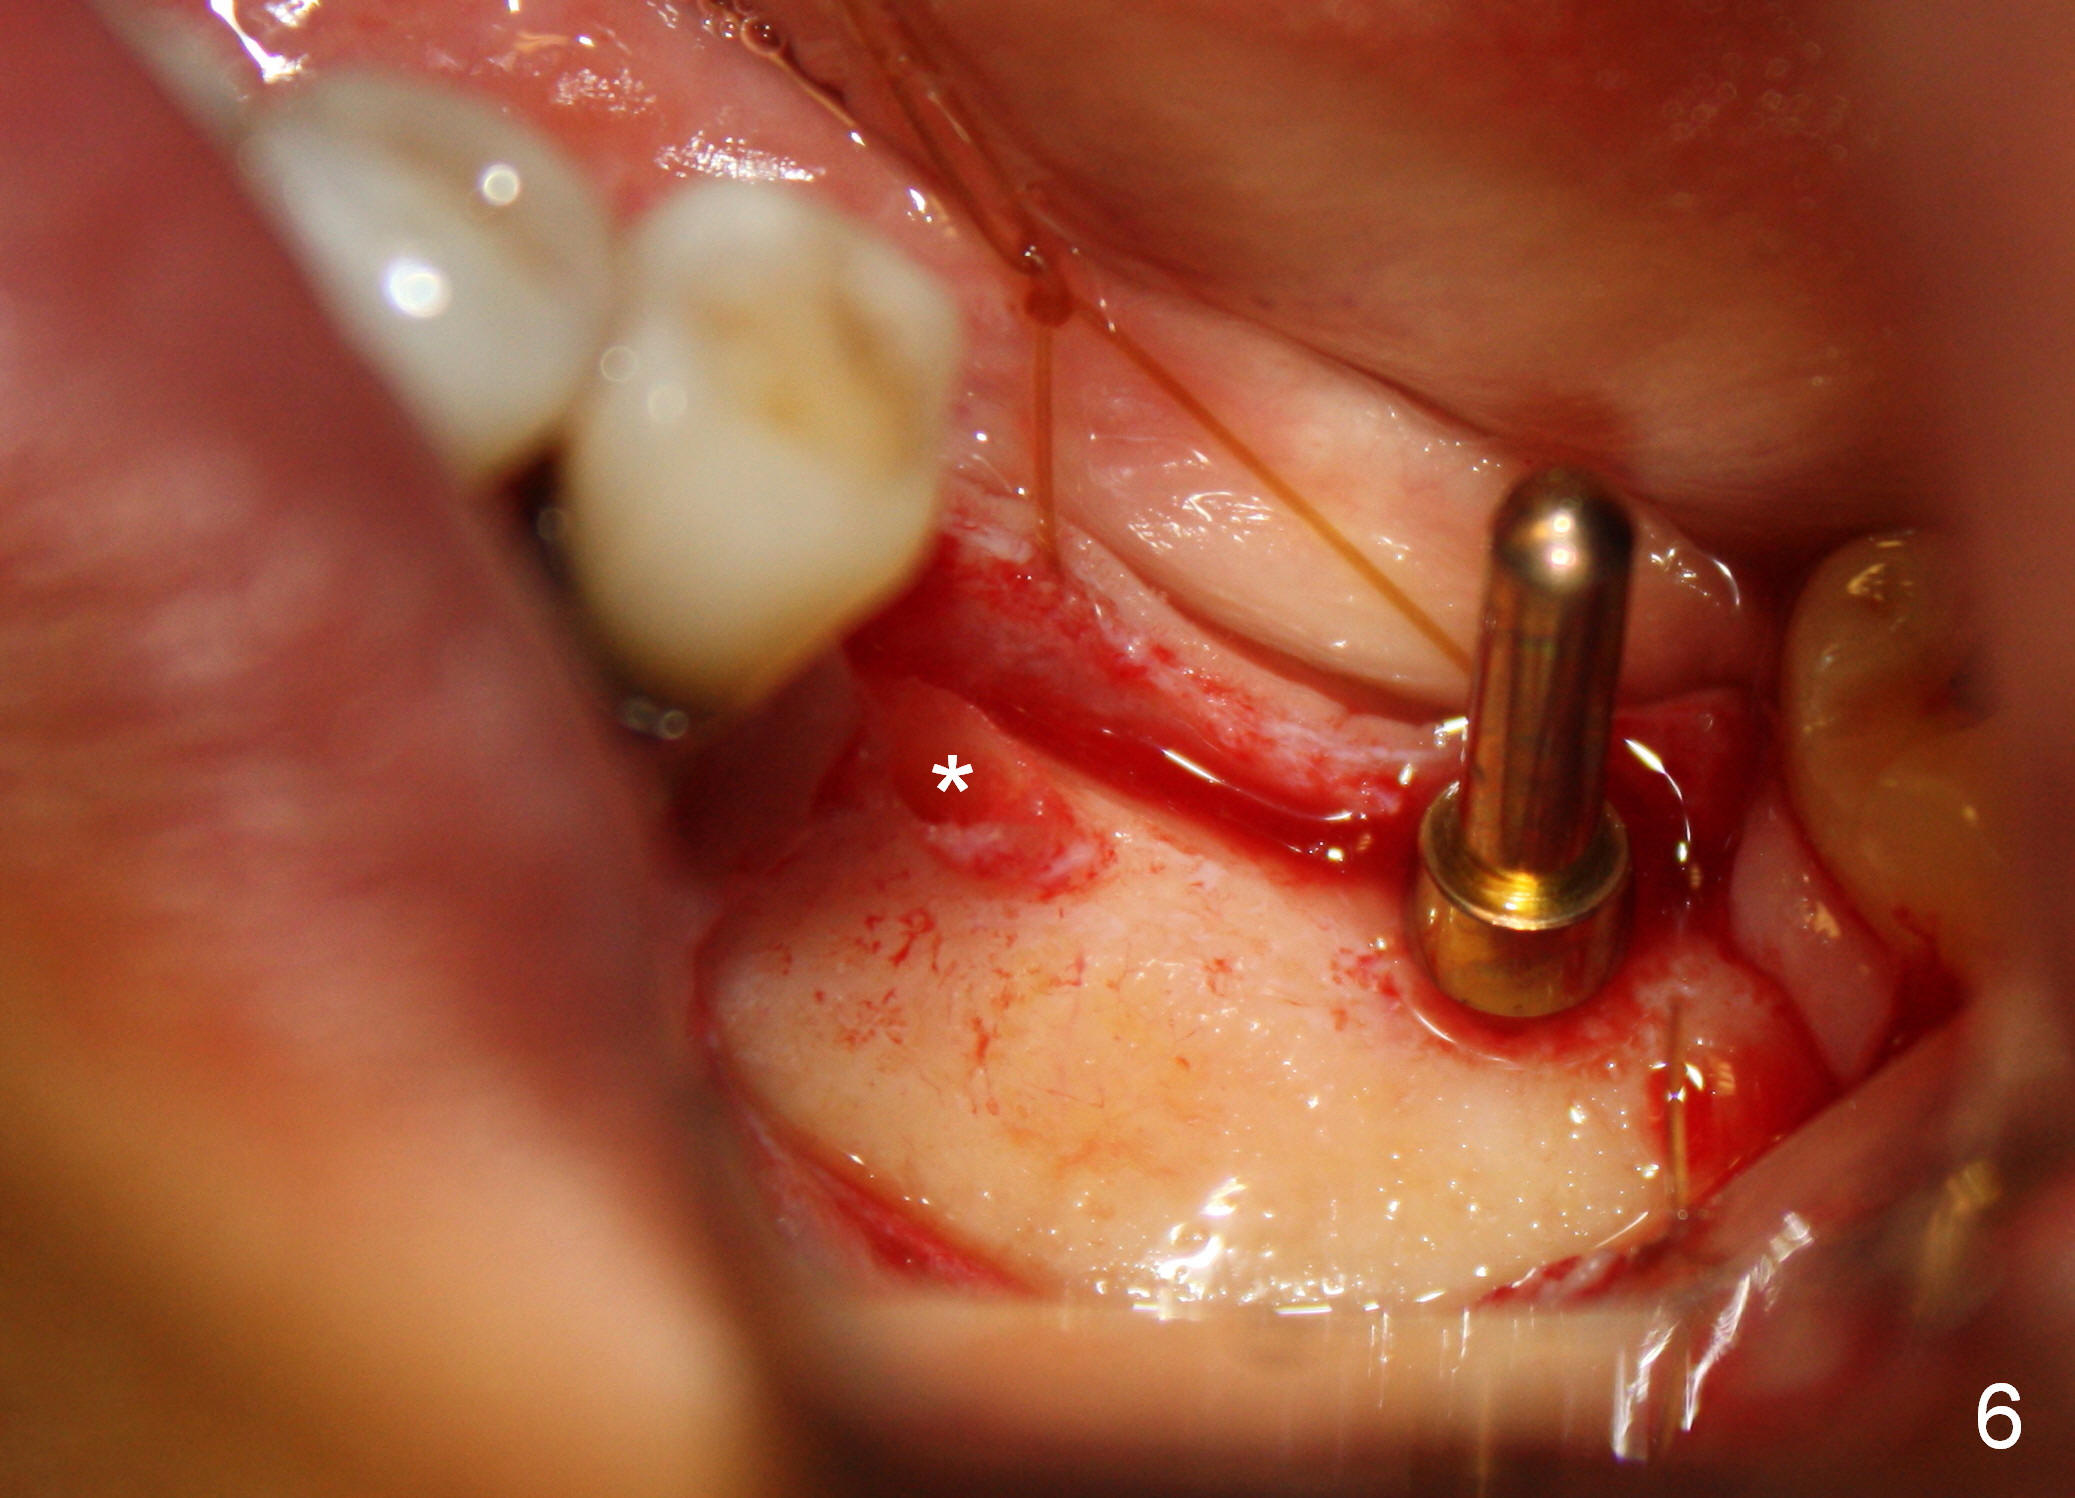

One year 2 months post root canal therapy at #20 (Fig.4), osteotomies are initiated at #18 and 19. The trajectory at #19 is subsequently corrected (Fig.5); that of #18 should be also corrected (arrow). The fact of the narrow ridge (Fig.6) is also ignored intraop. Without further adjustment, the osteotomies are enlarged (Fig.7) and the implants are placed (Fig.8: 4.5x14, 5x14 mm). As expected, the buccal coronal implant surface is exposed. The buccal plate is decorticated with placement of autogenous bone graft. Periodontal dressing is applied. Postop, the wound is infected with wound gapping. With irrigation, the wound finally heals.